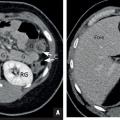

Un patient de 60 ans, éthylique chronique, vient pour amaigrissement et fatigue avec vomissements et distension abdominale. Le scanner au temps portal révèle une dysmorphie hépatique (contours bosselés) liée à une hépatopathie chronique (fig. 4 ; flèche blanche). S’y associent une ascite abondante (flèche noire), des voies de dérivation veineuse (tête de flèche noire) et une splénomégalie (tête de flèche blanche), traduisant une hypertension portale décompensée.

Un patient de 60 ans, éthylique chronique, vient pour amaigrissement et fatigue avec vomissements et distension abdominale. Le scanner au temps portal révèle une dysmorphie hépatique (contours bosselés) liée à une hépatopathie chronique (